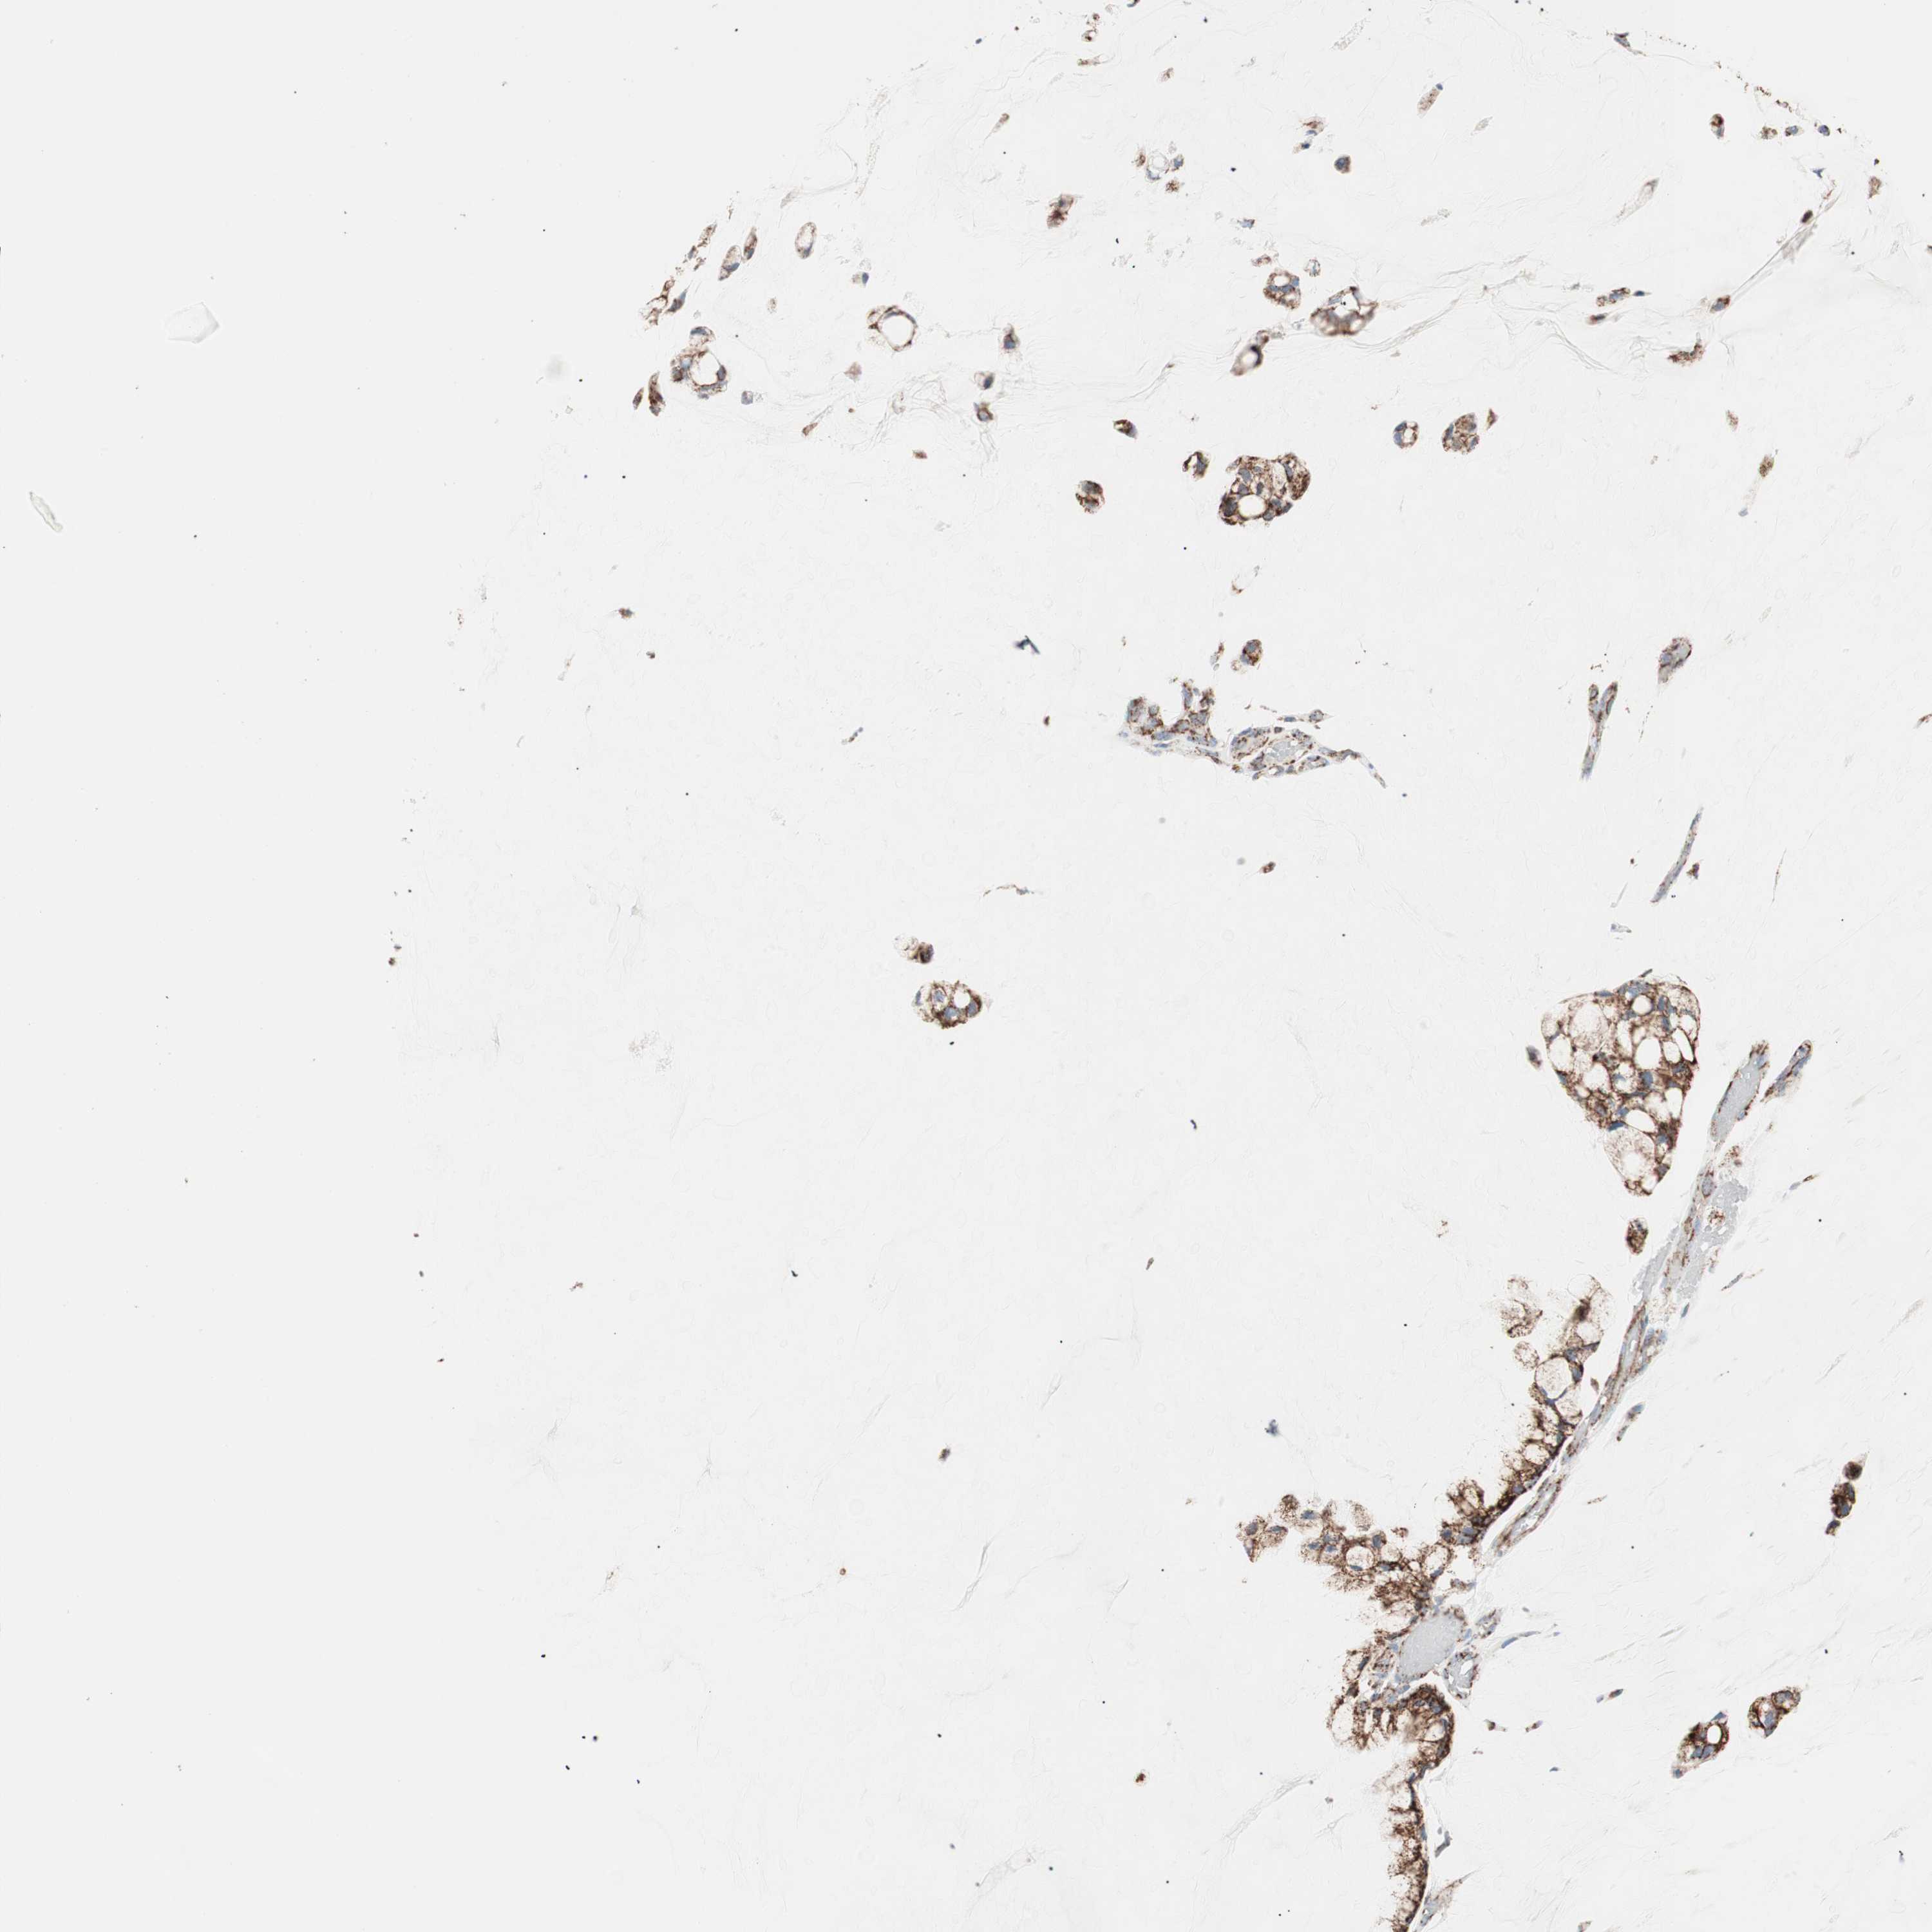

OVARIAN CANCER - Protein expressioni

A mouse-over function shows sample information and annotation data. Click on an image to view it in a full screen mode. Samples can be filtered based on level of antibody staining by selecting one or several of the following categories: high, medium, low and not detected. The assay and annotation is described here.

Note that samples used for immunohistochemistry by the Human Protein Atlas do not correspond to samples in the TCGA dataset.

Antibody stainingi

Antibody staining in the annotated cell types in the current human tissue is reported as not detected, low, medium, or high, based on conventional immunohistochemistry profiling in selected tissues. This score is based on the combination of the staining intensity and fraction of stained cells.

Each image is clickable and will lead to virtual microscopy that enables deeper exploration of all samples and also displays staining intensity scores, fraction scores and subcellular localization as well as patient and tissue information for each sample.

Antibody HPA011562

Antibody CAB005585

Cystadenocarcinoma, serous, NOS

Carcinoma, NOS

Carcinoma, endometroid